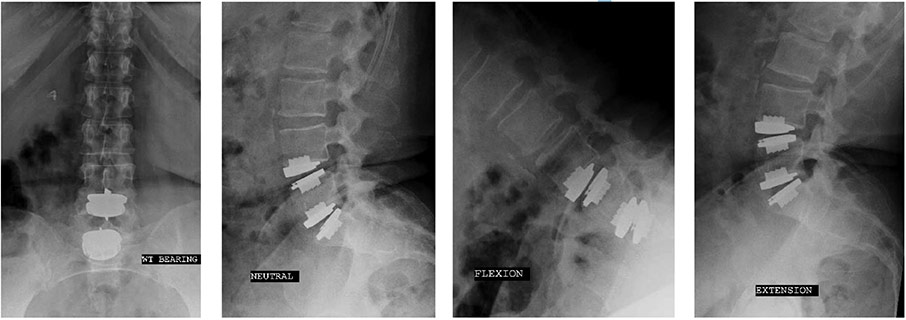

prodisc L Gallery

Click to enlarge image

The content shown on this page is provided courtesy of Centinel Spine. If you wish to learn more about prodisc L, visit their official website here.